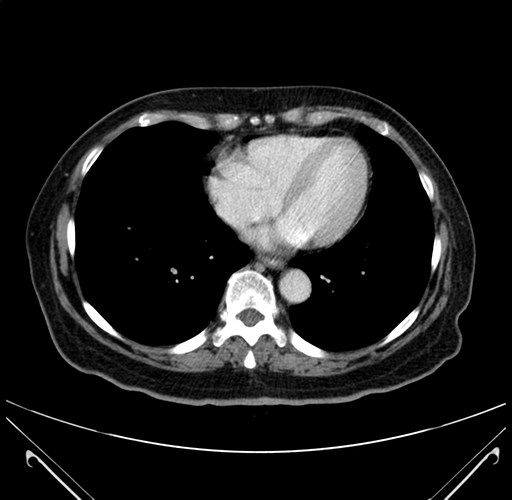

Pre-Chemo: Axial Venous

Axial Venous